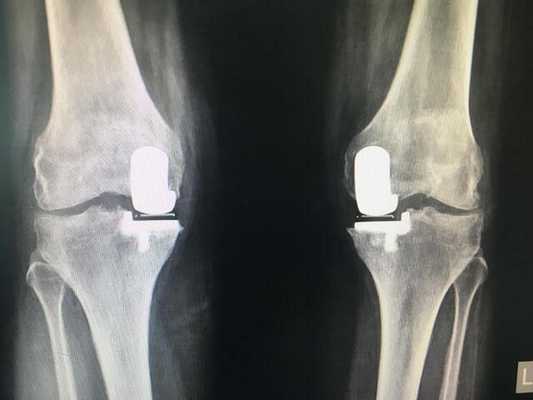

Имплант на рентгене.

Как это выглядит после операции.

Платформа импланта прослужившая пациенту 16 лет. Хороший результат.

Одномыщелковая замена сустава на рентгене.